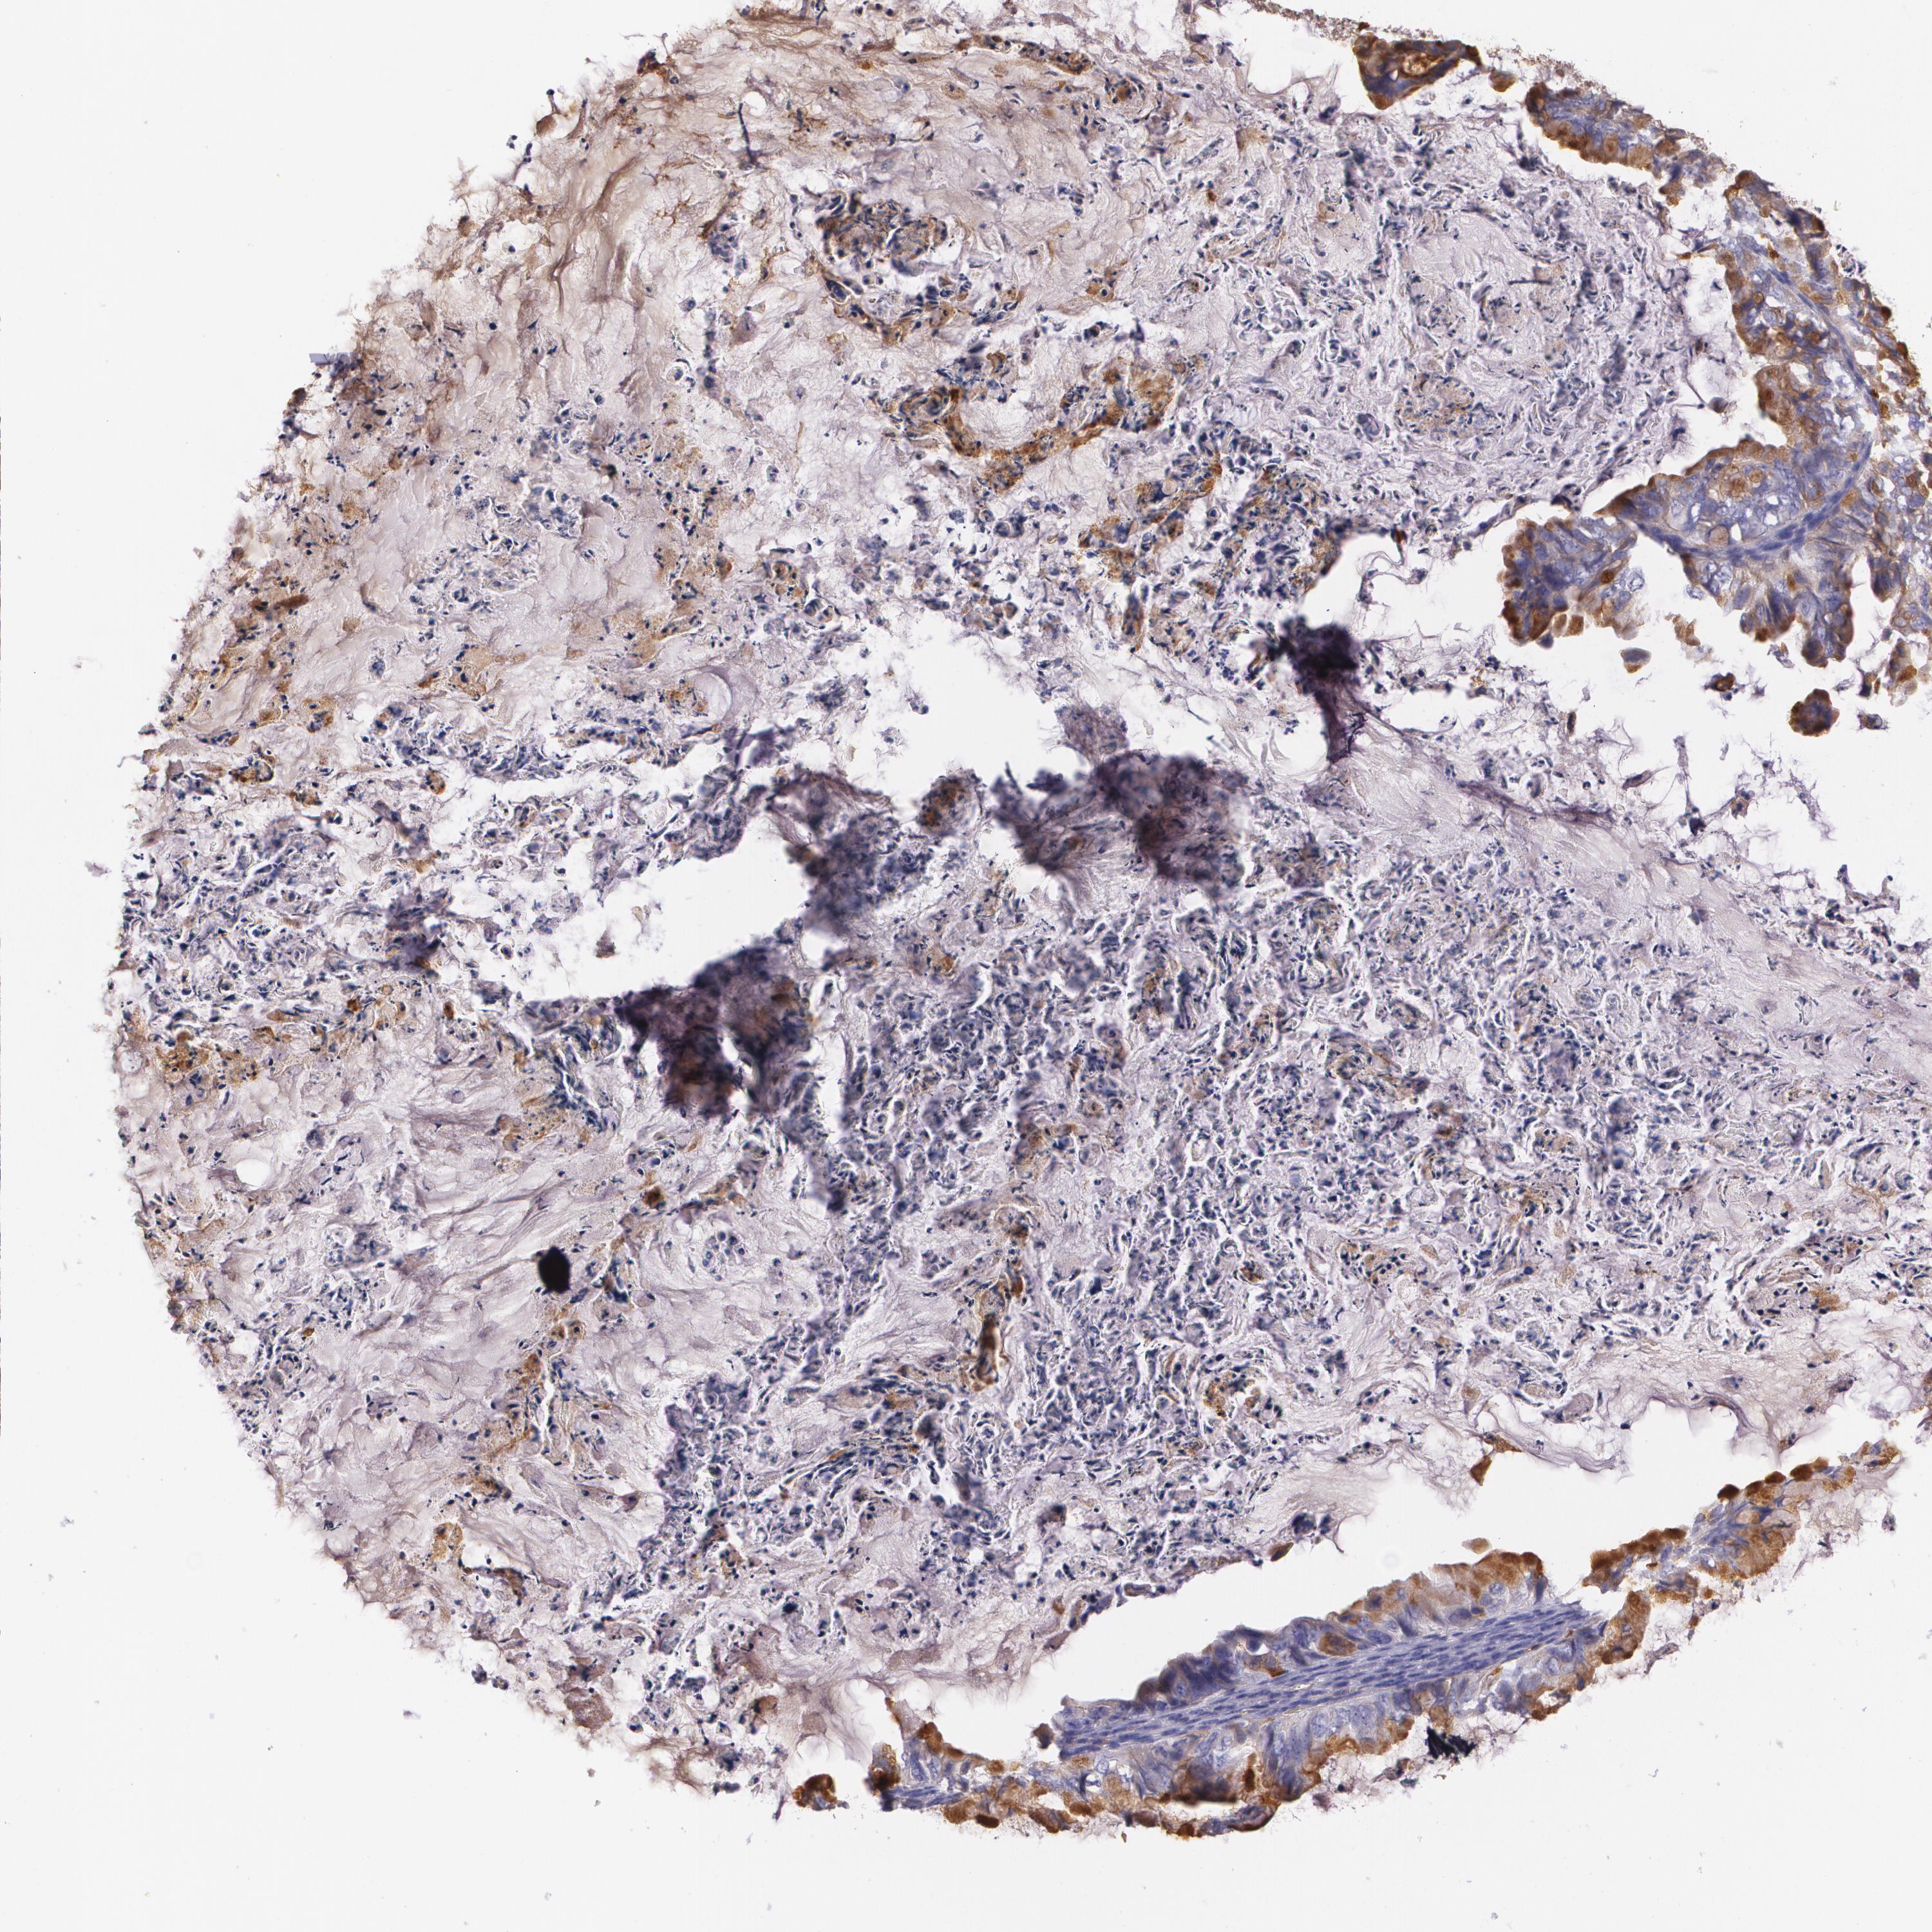

OVARIAN CANCER - Protein expressioni

A mouse-over function shows sample information and annotation data. Click on an image to view it in a full screen mode. Samples can be filtered based on level of antibody staining by selecting one or several of the following categories: high, medium, low and not detected. The assay and annotation is described here.

Note that samples used for immunohistochemistry by the Human Protein Atlas do not correspond to samples in the TCGA dataset.

Antibody stainingi

Antibody staining in the annotated cell types in the current human tissue is reported as not detected, low, medium, or high, based on conventional immunohistochemistry profiling in selected tissues. This score is based on the combination of the staining intensity and fraction of stained cells.

Each image is clickable and will lead to virtual microscopy that enables deeper exploration of all samples and also displays staining intensity scores, fraction scores and subcellular localization as well as patient and tissue information for each sample.

Antibody HPA006361

Antibody CAB002572

Staining

High

Medium

Low

Not detected

Intensity

Strong

Moderate

Weak

Negative

Quantity

>75%

75%-25%

<25%

None

Location

Nuclear

Cytoplasmic/membranous

Cytoplasmic/membranous,nuclear

Cystadenocarcinoma, serous, NOS

Carcinoma, endometroid

Carcinoma, NOS

Cystadenocarcinoma, mucinous, NOS